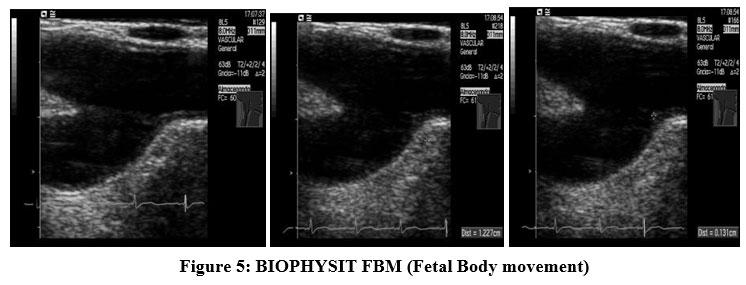

Which of the following are components of the biophysical profile (BPP)? Select all that apply

Explanation

Biophysical profile is a prenatal assessment tool that evaluates fetal well-being using real-time ultrasound and a non-stress test. It measures acute and chronic markers of hypoxia. Components scored include fetal breathing movements, body/limb movements, tone, amniotic fluid volume, and non-stress test. A normal score is 8–10. Normal amniotic fluid index (AFI) is 8–24 cm; normal single deepest pocket is 2–8 cm.

Rationale for correct answers

1. Fetal breathing movements are assessed by ultrasound; at least 1 episode of rhythmic breathing lasting ≥30 seconds in 30 minutes is normal.

3. Fetal movement is part of the BPP; ≥3 discrete body or limb movements within 30 minutes indicates normal activity.

4. Amniotic fluid volume reflects chronic uteroplacental function. A single vertical pocket ≥2 cm or AFI ≥5 cm is normal.

5. Non-stress test evaluates fetal heart rate accelerations with movement. Normal is ≥2 accelerations of ≥15 bpm lasting ≥15 seconds in 20 minutes.